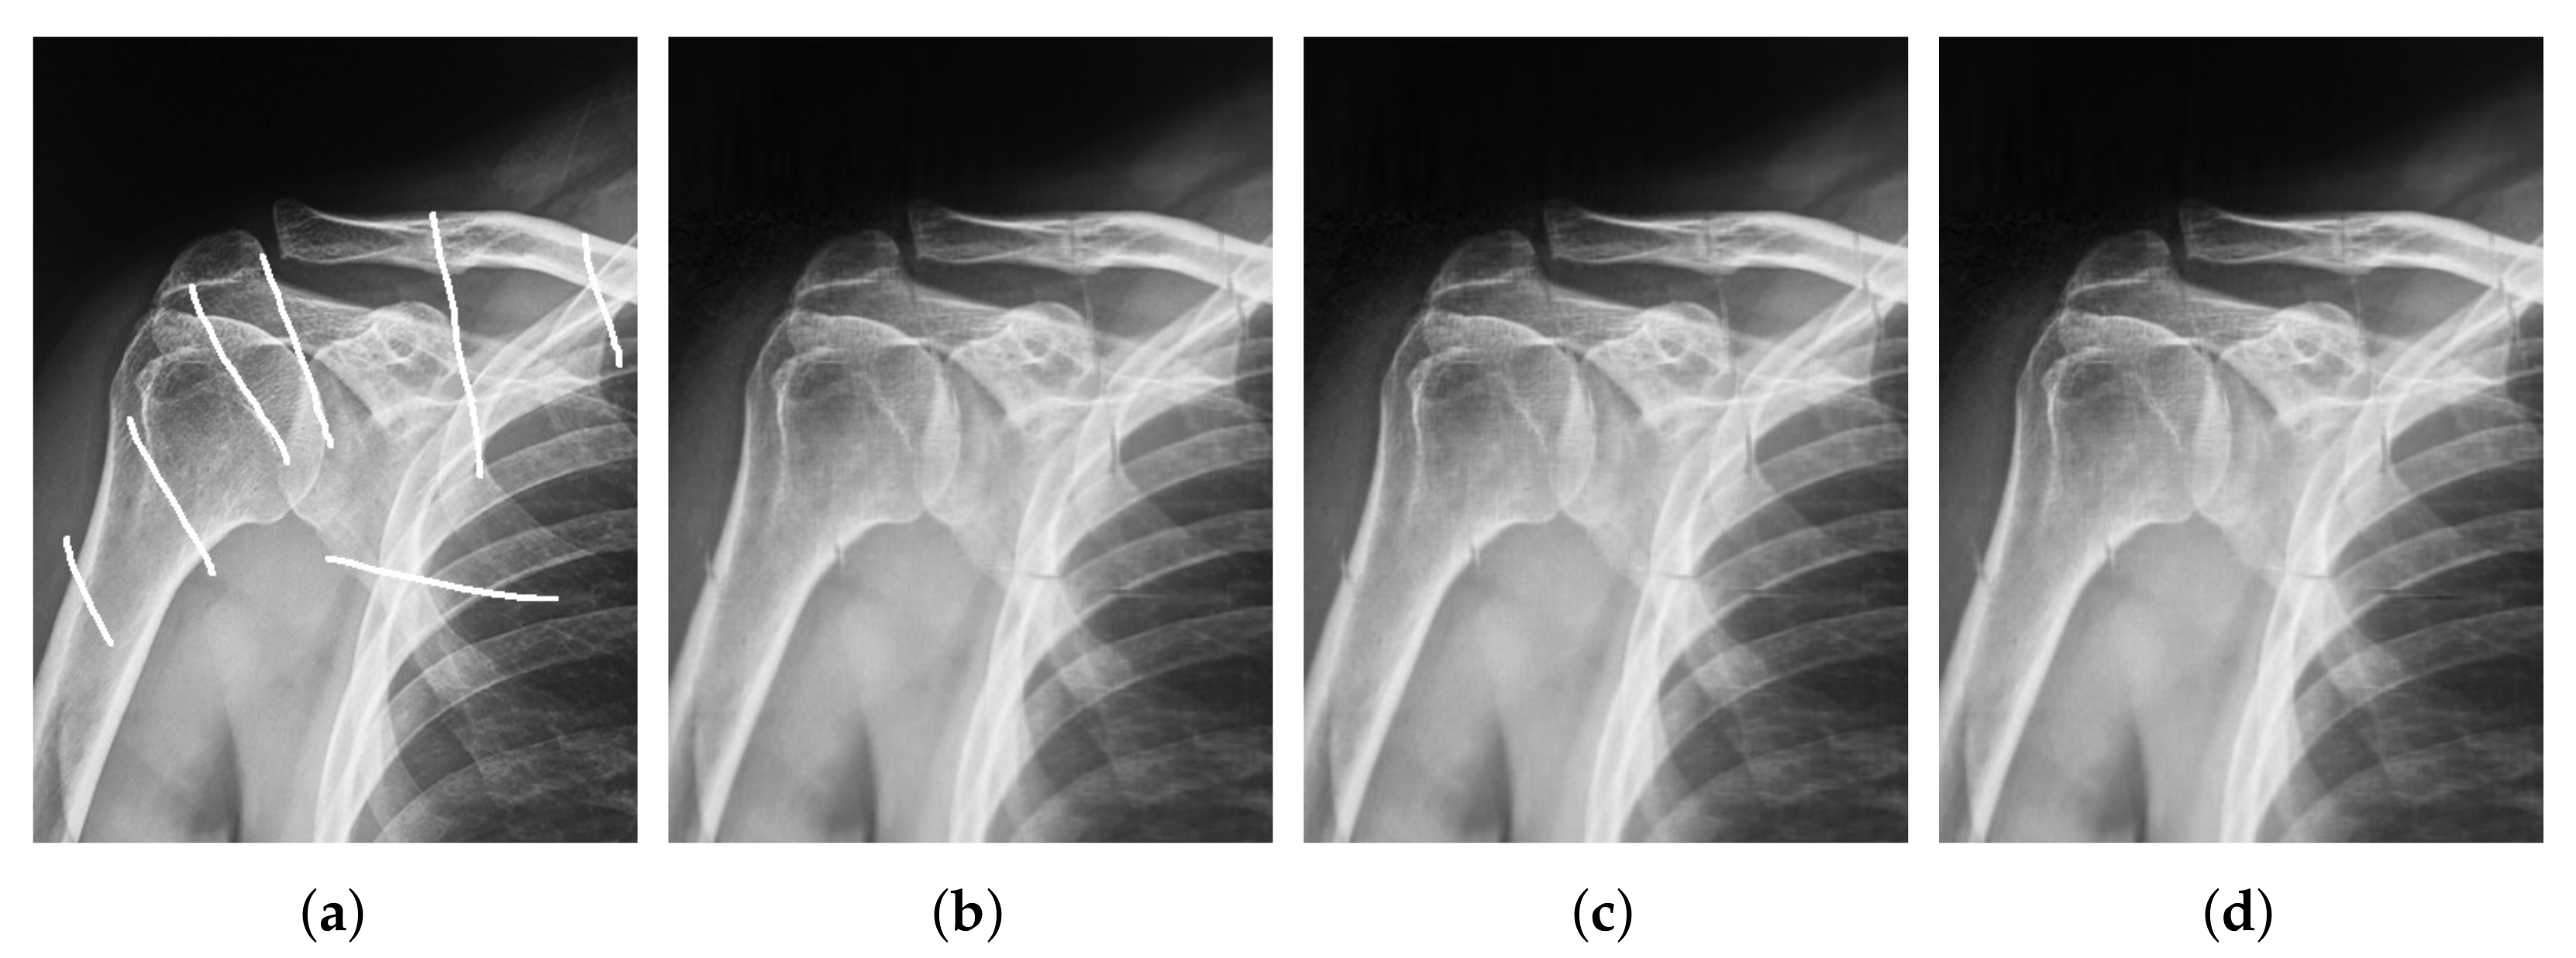

| Image Size | Image Size | |||

|---|---|---|---|---|

| SNR | SSIM | SNR | SSIM | |

| Algorithm 1 | 19.8276 | 0.9378 | 25.7210 | 0.9363 |

| Algorithm 2 | 20.4704 | 0.9402 | 26.2362 | 0.9373 |

| Algorithm 5 | 22.9158 | 0.9477 | 27.6581 | 0.9400 |